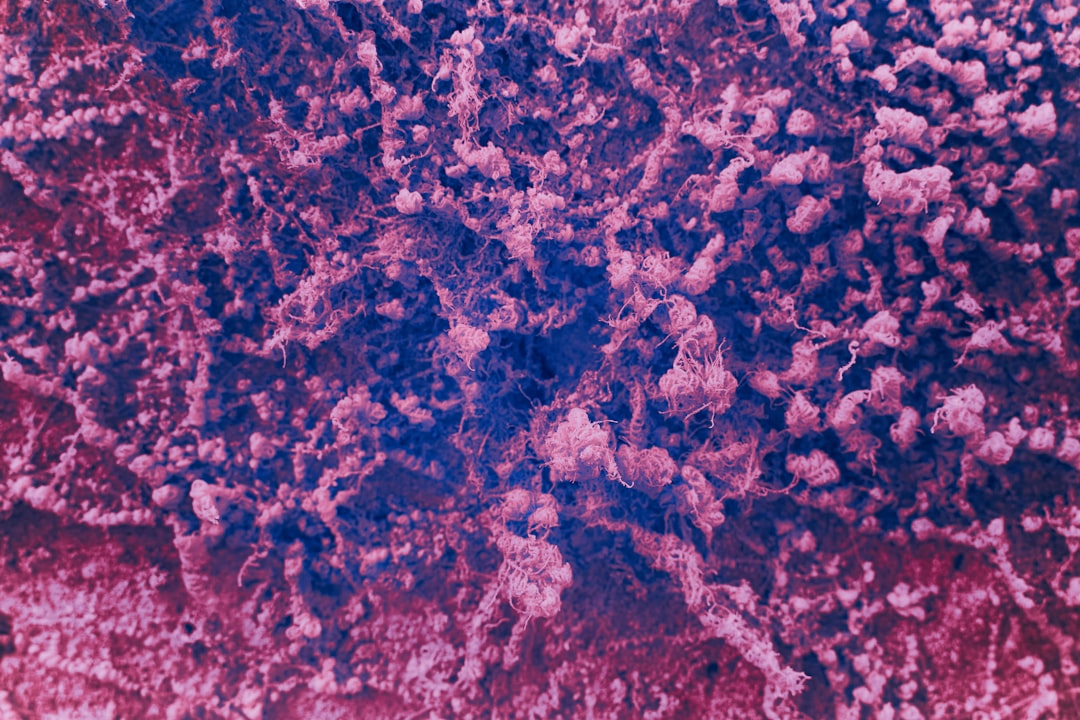

객담 검사는 결핵 검사방법 중 가장 전통적인 방식으로, 결핵균이 포함된 객담 샘플을 수집하여 검사합니다. 이 방법은 증상이 있다면 효과적으로 결핵 여부를 판단할 수 있으며, 일반적으로 2~3일의 시간이 소요됩니다. 검사를 통해 세균의 존재 여부를 확인하고, 추가적인 검사가 필요할 경우 확진을 위한 기초 데이터를 제공합니다.